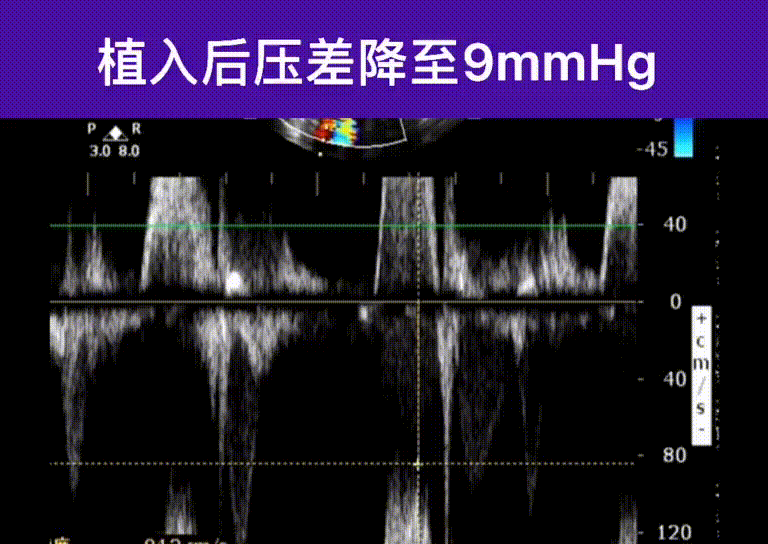

瓣膜植入后工作稳定,未出现冠脉阻挡,术后即刻清醒,血流动力学得到明显改善,为患者生命健康带来福音。

术后即刻评估: